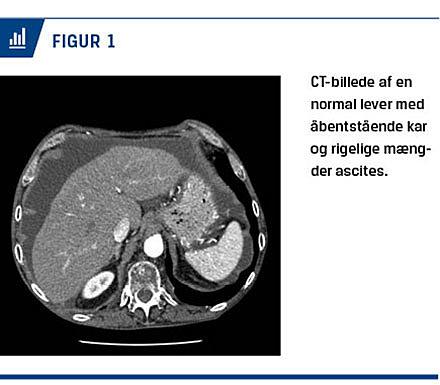

Pga. behov for hyppige ascitestapninger blev patienten henvist til en hepatologisk afdeling til vurdering af anlæggelse af en transjugulær intrahepatisk portosystemisk shunt. Levervenekaterisationen viste et normalt portaltryk på 7 mmHg. CT af leveren viste en normal lever og ascites (Figur 1). En urinstiks viste +3 for protein, og døgnurinsopsamling viste proteinuri på 8,3 g/døgn. Der var negative resultater ved bestemmelse af antinukleære antistoffer, antineutrofile cytoplasmatiske antistoffer og M-komponent samt normalt niveau af glykeret hæmoglobin. Blodtrykket var 110/63 mmHg, og der var ingen deklive ødemer. Man havde mistanke om nefrotisk syndrom som årsag til den recidiverende ascites. En nyrebiopsi viste MG. Anti-fosfolipase-A2-receptor (PLA2R)-niveauet var forhøjet, hvilket tydede på primær MG pga. autoimmunsygdom. Udredning for sekundære årsager (hiv, hepatitis og malignitet) var negativ. Patienten blev pga. det høje proteinuri niveau og den recidiverende ascites behandlet med tablet prednisolon 40 mg samt tablet azathioprin 100 mg dagligt.

Hos patienten i sygehistorien bestod det nefrotiske syndrom i den recidiverende ascites, hypoalbuminæmi og proteinuri. Patienten havde normale levertal, ingen øsofagusvaricer og en normalt udseende lever på CT-billeder, men pga. hans alkoholoverforbrug havde man initialt mistanke om cirrose som årsag til hans ascites. En simpel urinstiks samt undersøgelse af albumin-kreatinin-ratio og S-ascitesalbumingradient manglede dog i udredningen. Patienten blev heller ikke behandlet med en aldosteronantagonist [1].